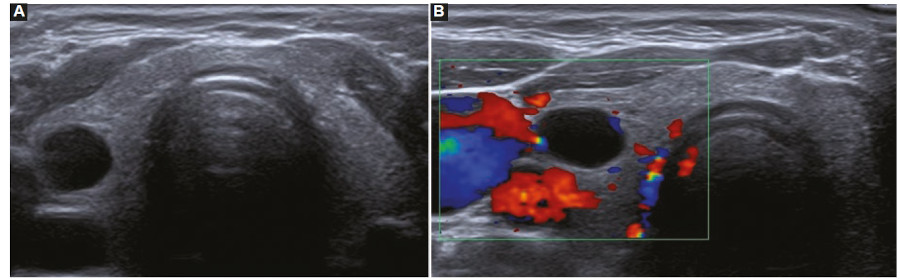

Vascularización

La vascularización se evalúa con la herramienta de Doppler color, y se debe determinar si esta se encuentra ausente (Fig. 18) o aumentada en el nódulo en relación con el parénquima tiroideo. La vascularización aumentada puede presentar dos patrones: central (Fig. 19) y periférico (Fig. 20), siendo el aumento de la vascularización central con disposición caótica la que presenta mayor riesgo de malignidad2,14,19,22,23,24. Un patrón vascular periférico se asocia mayormente con benignidad15,18, aunque algunos autores han calificado a la vascularización como una característica no significativa para diferenciar nódulos benignos de malignos2,3,14,16.